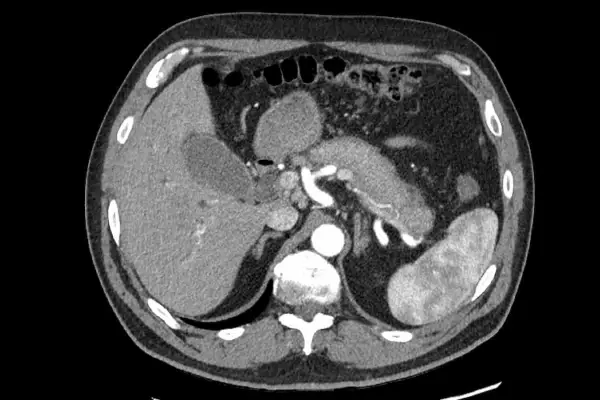

- Ultrasound & CT Scan: Visualize pancreatic structure and detect cysts, tumors, or inflammation.

- MRI & MRCP (Magnetic Resonance Cholangiopancreatography): Detailed imaging of the pancreas and bile ducts for accurate diagnosis.

- Endoscopic Ultrasound (EUS): Minimally invasive method to examine pancreatic tissue and guide biopsies.

Our advanced diagnostic approach allows for early detection of serious conditions, including pancreatic cancer, improving treatment outcomes.